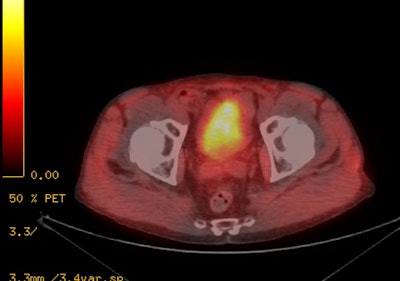

|

18F-Fluciclovine for

biochemical recurrence: The patient below had

undergone prior external XRT for treatment of prostate

cancer and had suspicion for biochemical recurrence based

on slowly rising PSA. The exam demonstrated focal uptake

in the right prostate adjacent to an internal fudicial

marker. The finding is seen on both AC (second image) and

non-AC images (third image) which confirms the finding is

not an artifact related to the beam hardening associated

with the marker. The referring physician elected not to

pursue the exam finding and was primarily concerned with

the presence of nodal disease which was not evident on the

study. |